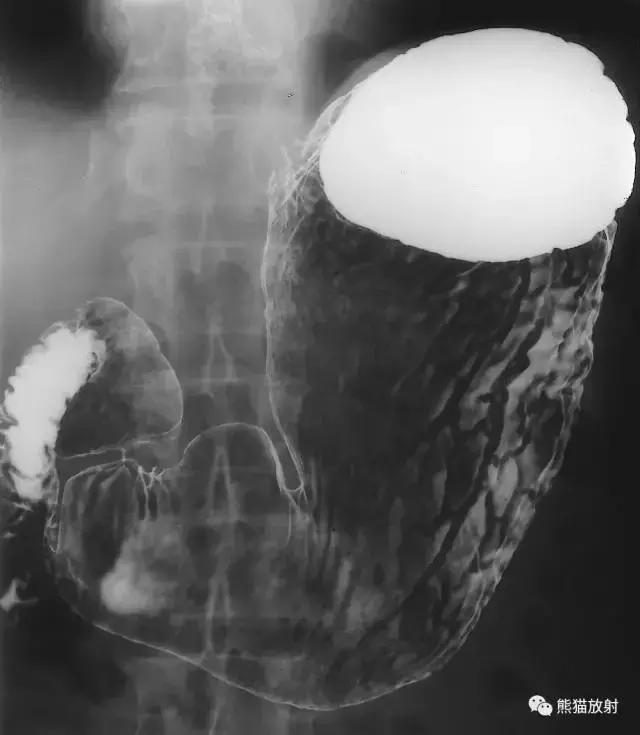

七、胃和小肠

图13 胃和小肠造影

图14 胃和小肠解剖示意图。1 十二指肠球部,2 幽门窦,3 十二指肠空肠曲,4 结肠,5 胃体,6 十二指肠降段,7 十二指肠升段,8 十二指肠水平段,9 空肠,10 回肠